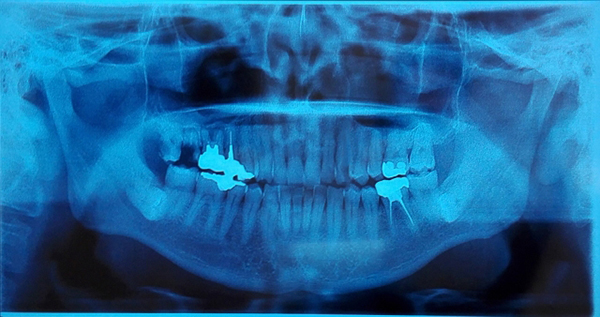

抜歯をする場合、どの位置の歯がどのような埋まり方をしているかにより、治療の難易度が変わってきます。

大人の歯が、歯ぐきや歯槽骨の中に埋まっている状態が埋伏歯と呼ばれます。

必要があれば、歯茎を切開して歯を取り出します。

埋伏歯の周りの神経や血管の位置によっては、一般的な抜歯と比べはるかに高い技術が要求されます。

当院では最も困難なケースである水平埋伏智歯の抜歯も行っております。